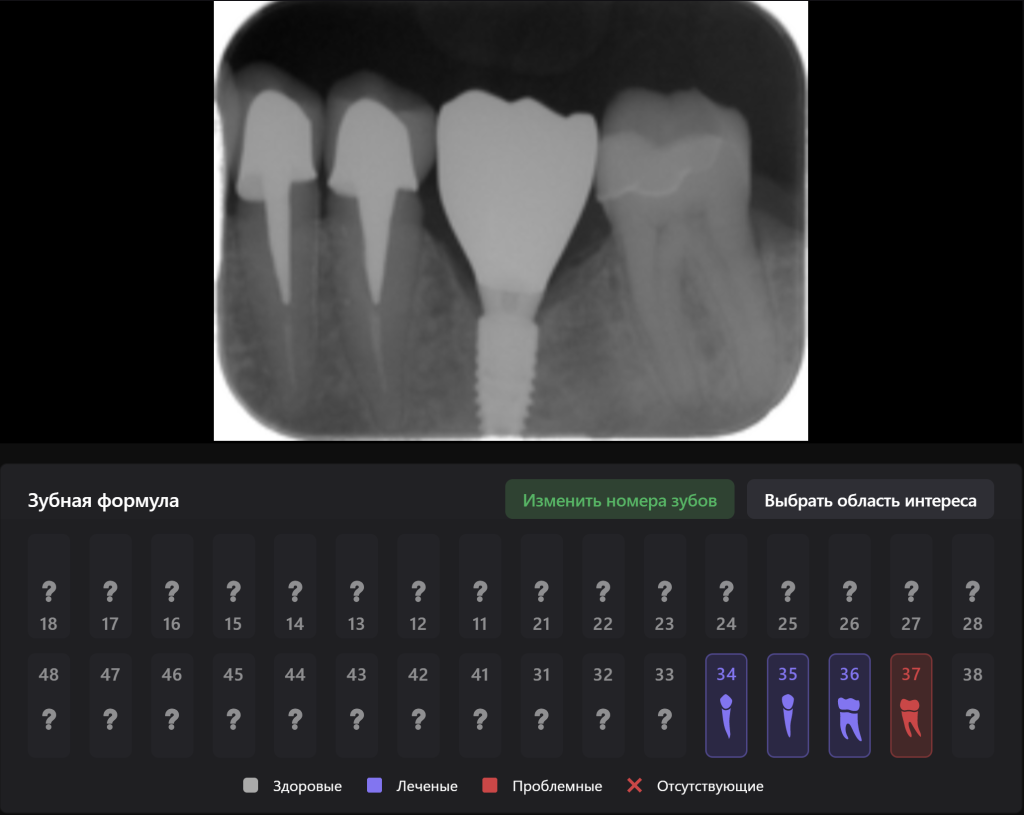

Интраоральная рентгенограмма, загруженная в FMX модуль Diagnocat демонстрирует благоприятную ортопедическую позицию имплантата